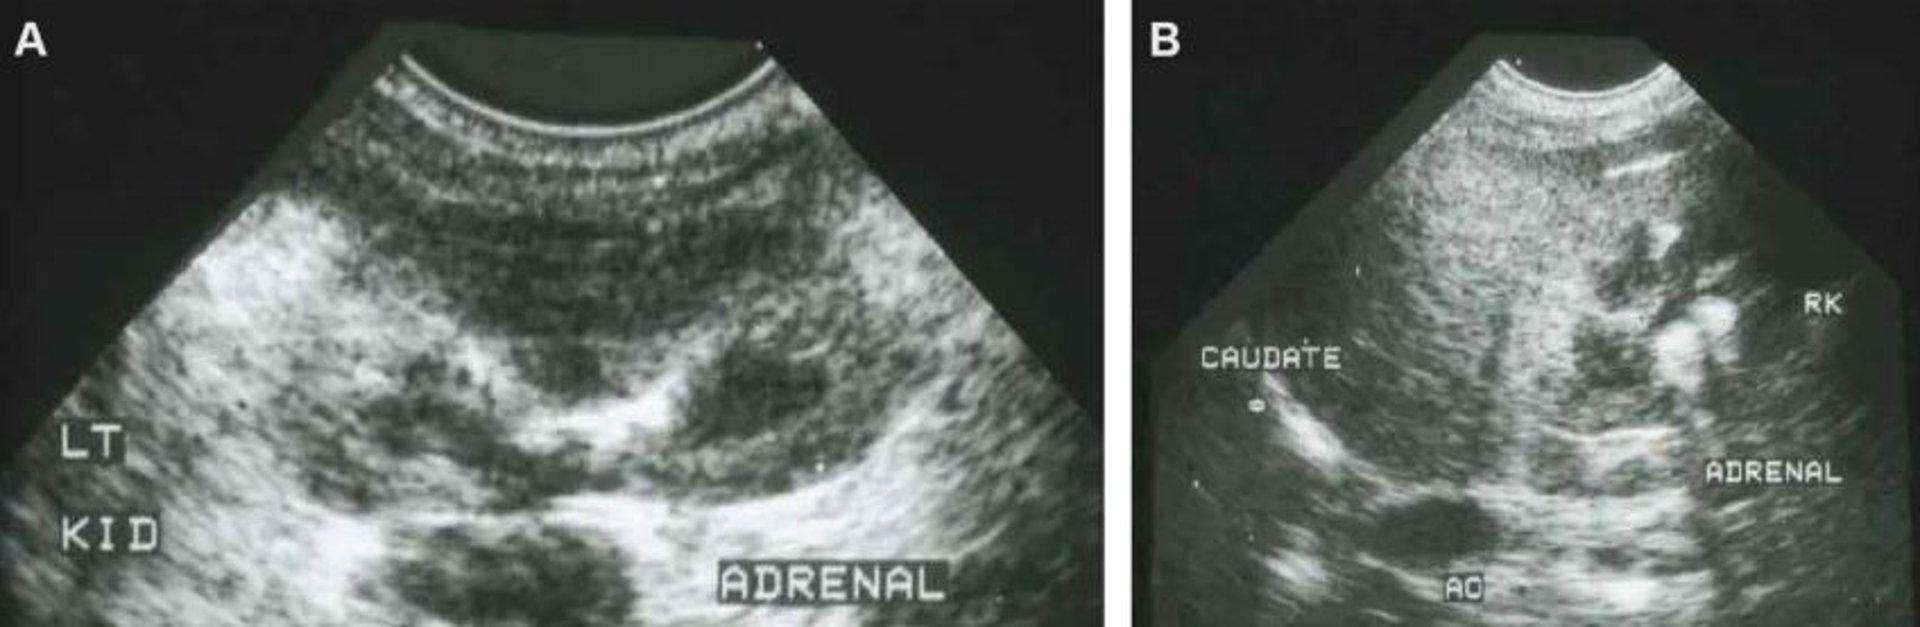

Normal adrenal glands, ultrasonograms, dog

Ultrasonographic images showing normal left (A) and right (B) adrenal glands in a dog. AO, aorta; LT KID, left kidney; RK, right kidney.

Courtesy of Dr. Deborah Greco.